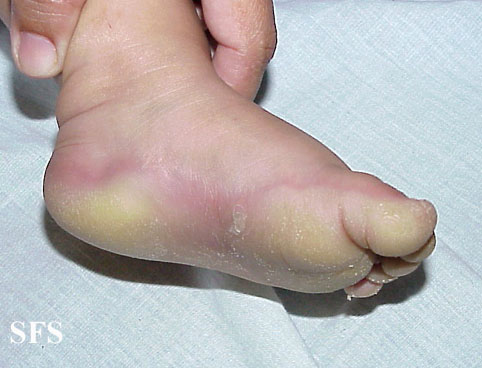

difuse palmoplantar keratoderma